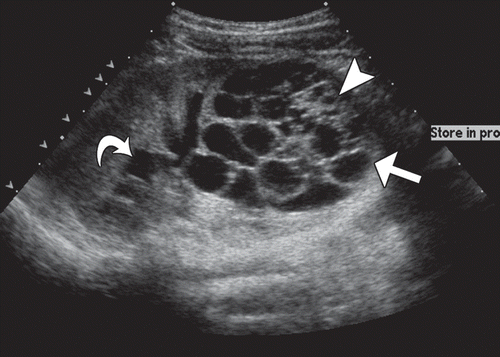

Macroscopic cysts without communication (unable to excrete into collecting system)

MULTICYSTIC DYSPLASTIC KIDNEY

0-3

Benig